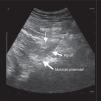

El síndrome piriforme es una causa poco frecuente de dolor de espalda y miembros inferiores. Algunas de las opciones de tratamiento incluyen la inyección del músculo piriforme con anestésicos locales y corticoides. Se han descrito varias técnicas de inyección. Las técnicas ecoguiadas permiten la visualización directa del músculo y la inyección en tiempo real. Se presenta una serie de 5 pacientes cuya clínica es compatible con síndrome piriforme, que no han mejorado tras tratamiento farmacológico. Se optó por la inyección del músculo piriforme con anestésicos locales y corticoides mediante un nuevo abordaje ecoguiado más sencillo técnicamente, basado en la técnica estándar. En los 5 pacientes se apreció una mejoría del dolor medido por la escala verbal numérica tras la inyección. Solo en un caso se presentó como complicación una ciatalgia que mejoró espontáneamente en 10 días. En los demás pacientes no se observaron complicaciones tras la inyección. Se describe una variante de la técnica ecoguiada recomendada en la inyección del músculo piriforme, más sencilla de realizar, con un buen perfil de seguridad y con buenos resultados clínicos.

Piriformis syndrome is an uncommon cause of buttock and leg pain. Some treatment options include the injection of piriformis muscle with local anesthetic and steroids. Various techniques for piriformis muscle injection have been described. Ultrasound allows direct visualization and real time injection of the piriformis muscle. We describe 5 consecutive patients, diagnosed of piriformis syndrome with no improvement after pharmacological treatment. Piriformis muscle injection with local anesthetics and steroids was performed using an ultrasound technique based on a standard technique. All 5 patients have improved their pain measured by numeric verbal scale. One patient had a sciatic after injection that improved in 10 days spontaneously. We describe an ultrasound-guided piriformis muscle injection that has the advantages of being effective, simple, and safe.